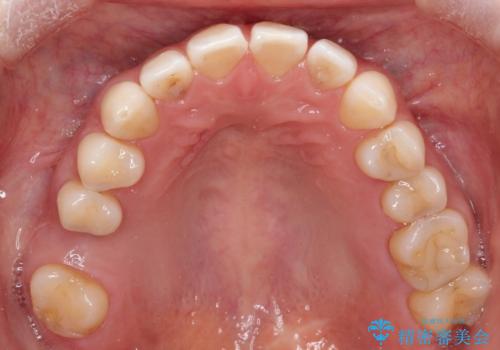

【インビザラインで再矯正】マウスピース矯正で隙間を閉じたい

- 過去に矯正を行ったあと、前歯の後戻りを主訴に来院されました。

マウスピース矯正にて隙間を閉じる計画をたて、治療を行いました。